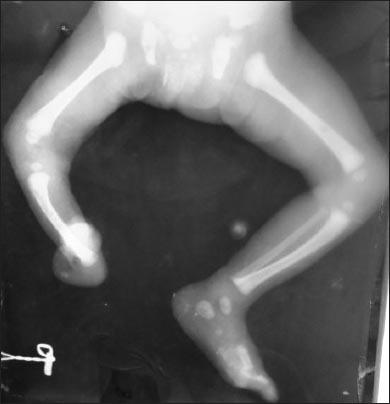

戈尔茨综合征:一名患有缺指(趾)畸形和皮肤病变的新生儿。

Goltz syndrome: a newborn with ectrodactyly and skin lesions.

Goltz syndrome or Focal Dermal Hypoplasia is a rare multisystem disorder, involving all the three germ cell layers. The disease is thought to be inherited in X-linked dominant fashion with heterogeneous mutations of the PORCN gene at Xp11.23 locus. Majority of the cases are sporadic, mainly due to postzygotic somatic mutations. The clinical spectrum includes characteristic cutaneous manifestations, multiple skeletal anomalies, and involvement of the eyes, hair, nails, kidneys, and so on. Considerable variability is noted in the clinical expression of the disease probably due to genomic mosaicism. Around 300 cases of Goltz syndrome have been reported in the literature. Here, we report such a case with characteristic skin lesions, multiple bony defects, distinctive facial features, coloboma of iris, and bilateral hydronephrosis. The diagnosis was evident immediately after birth due to the characteristic clinical picture of the baby.

戈尔茨综合征或局灶性真皮发育不全是一种罕见的多系统疾病,累及所有三个胚层。该疾病被认为以X连锁显性方式遗传,在Xp11.23位点的PORCN基因存在异质性突变。大多数病例为散发性,主要是由于合子后体细胞突变。临床谱包括特征性皮肤表现、多发性骨骼异常以及眼睛、毛发、指甲、肾脏等受累。由于基因组镶嵌现象,该疾病的临床表型存在相当大的变异性。文献中已报道约300例戈尔茨综合征病例。在此,我们报告一例具有特征性皮肤病变、多发性骨缺损、独特面部特征、虹膜缺损和双侧肾积水的病例。由于婴儿具有特征性临床表现,出生后诊断立即明确。